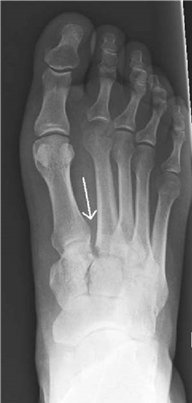

What do you see and which joint is involved?

This AP radiograph shows disruption at the tarso-metatarsal joints otherwise known as a Lisfranc injury.

What is the Lisfranc joint?

This consists of three cuneiform and two cuboid metatarsal articulations. Joint stability is provided by strong ligaments and the recessing of the second metatarsal head. The Lisfranc ligament runs from the base of the second metatarsal to the medial cuneiform.

How do you describe Lisfranc injuries and which type is this?

T ype A is a complete uniplanar dislocation involving the whole joint. A type B injury describes a partial dislocation, either medial or lateral. Type C injuries are divergent dislocations.

In this case there appears to be a lateral type B injury.

This is an isolated injury. How would you proceed?

I would provide analgesia and elevation with a resting splint, including foot/ankle, but allowing room for swelling. I would observe for evidence of compartment syndrome and obtain further radiographic views and CT scan. I would wait for the swelling to reduce before considering surgery. Skin softening and wrinkling suggests that swelling is receding.

What do you look for on plain radiographs?

O n an AP view the second metatarsal and medial cuneiform medial borders should align. On an oblique view the medial borders of the fourth metatarsal and cuboid should align. I would also look for the fl eck sign which implies an avulsion of the Lisfranc ligament.

What is your operative plan for this fracture?

I would plan to openly reduce and fi x with screws, starting with the second metatarsal reduction. I would employ two skin incisions, one over the fi rst web space, the second over the fourth metatarsal.

What are you going to say to this patient about his long-term outcome?

I would warn him that even if his surgery goes well and things heal as planned there remains a 30 % chance of post-traumatic osteoarthritis.